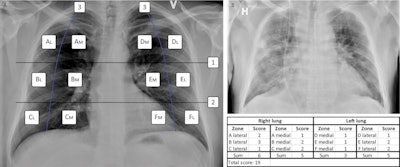

(A) The MBrixia scoring system. Box 1 and 2 mark the horizontal division corresponding to the inferior wall of the aortic wall, and the inferior wall of the right pulmonary vein, respectively, creating three zones in each lung: A, B, C, D, E and F. Box 3 marks the vertical line drawn from the pulmonary apices to the diaphragm, creating further division into medial (M) and lateral (L) zones. (B) A clinical example of a chest x-ray image scored using the MBrixia score. Image courtesy of Scientific Reports through CC BY 4.0 International License.

(A) The MBrixia scoring system. Box 1 and 2 mark the horizontal division corresponding to the inferior wall of the aortic wall, and the inferior wall of the right pulmonary vein, respectively, creating three zones in each lung: A, B, C, D, E and F. Box 3 marks the vertical line drawn from the pulmonary apices to the diaphragm, creating further division into medial (M) and lateral (L) zones. (B) A clinical example of a chest x-ray image scored using the MBrixia score. Image courtesy of Scientific Reports through CC BY 4.0 International License.The group applied the MBrixia score to 290 chest x-ray images acquired from 37 COVID-19 patients between May 4 and June 5, 2020. Twenty-two (59.5%) patients were admitted to the intensive care unit and 10 (27%) died during follow-up. Respiratory support was categorized according to severity based on an ordinal scale of five levels.